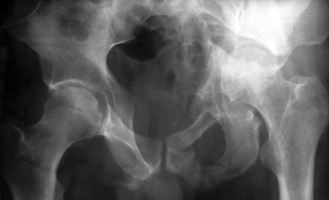

Перелом от августа 2003г. Признаков консолидации не видно. Коллеги, интересно Ваше мнение о тактике лечения. Мужчина 48 лет. В августе 2003г ДТП. В одном из ЛУ диагностирован перелом лонной и седалищной костей с обеих сторон, дна вертлужной впадины слева с центральным вывихом бедра. Предпринято следующее лечение: 2 недели на скелетном вытяжении, далее предписано ходить с доп. опорой на костыли без нагрузки на левую ногу. Еще через 2 недели выписан. По настоящее время ходит с костылями. При контрольном обследовании, включающем КТ выявлен еще перелом подвздошной кости слева, признаков консолидации переломов не отмечено, везде виден явный диастаз с вялой периостальной реакцией. Положение головки левого бедра только ужудшилось - протрузия ее увеличилась по сравнению с августом. Пациент ходит с трудом, но ходит. Укорочение левой ноги. Хотелось бы посоветоваться, что бы вы предприняли в данном случае?

На представленной запирательной проекции четко виден обычный высокий двухколонный перелом левой вертлужной впадины, при котором часто имеется вторичная конгруентность сустава, как видимо и в этом случае.

Для подтверждения конгруентности необходма прямая и подвздошная проекции.